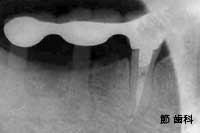

⑦ この症例は、右下奥の3本を連続して喪失しているケースで、同部位にU字型の“人工サファイヤ”タイプのインプラントを埋入し、隣在する歯とブリッジ状に連結することで、欠損補綴を行っています。

info_1